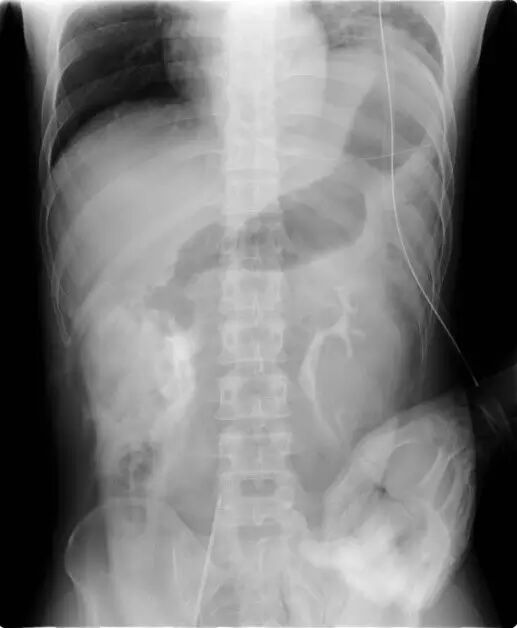

在重症监护室中,患者血压110/60mmHg,心率106次/分,但术后9小时仍未排尿。后行腹部X线检查。肾盂输尿管结合处检测到造影材料渗漏,再次CT发现双侧肾周腹膜后对比度增强(图2)。对其进行膀胱镜检查和双侧逆行肾盂造影,显示双侧输尿管完全破裂,无法植入输尿管支架。诊断性剖腹示双侧肾盂输尿管结合处完全破裂。双侧植入双J输尿管支架,并行肾盂输尿管吻合术。患者术后进展良好,术后第23天出院。

图1